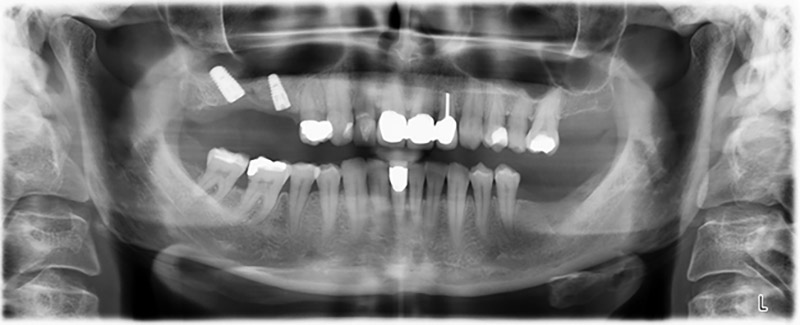

Unos seis meses después de la extracción de las piezas 16 y 14 se realizó una tomografía digital de volúmenes (DVT, Planmeca) para realizar una planificación adecuada y reducir los riesgos al mínimo. En este punto se constató que el hueso no se había regenerado en la cantidad deseada (figuras 2 a 7).